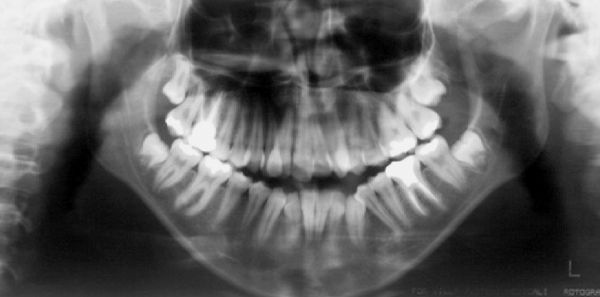

Radiografia inicial